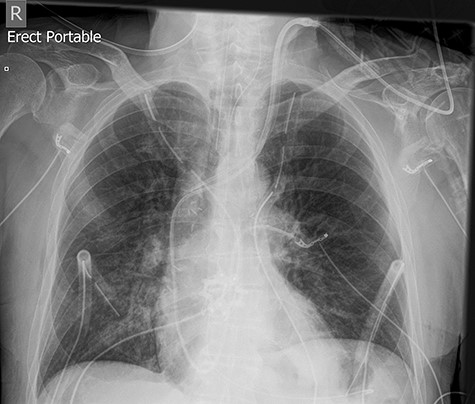

The left basal chest drain was removed without incident on Day 5. However, the nurse encountered resistance during attempted removal of the right basal chest drain. The intern was subsequently notified. Resistance was also encountered by the intern during a further attempt to remove the chest drain. A chest X-ray performed earlier in the day was reviewed (Fig. 2). It demonstrated kinking of the drain around a rib. The intern altered the direction of traction in order to account for the kinking but, during gentle traction, the chest drain fractured at the 14-cm mark (Fig. 3) and became retained within the right hemithorax (Fig. 4). The thoracostomy wound was closed and senior help was immediately sought.

Chest X-ray demonstrating the retained chest tube segment on the right side.